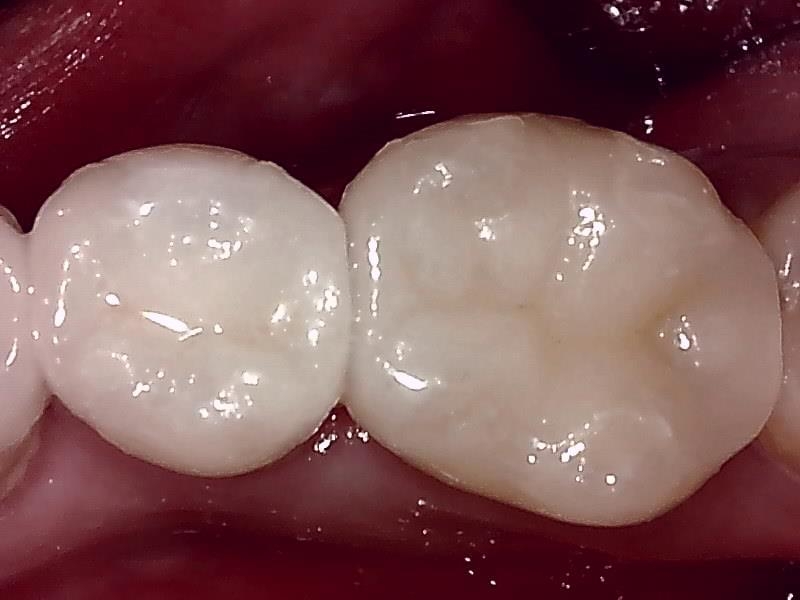

写真; セラミックインレー装着後の歯冠の仕上がり(咬合面観)